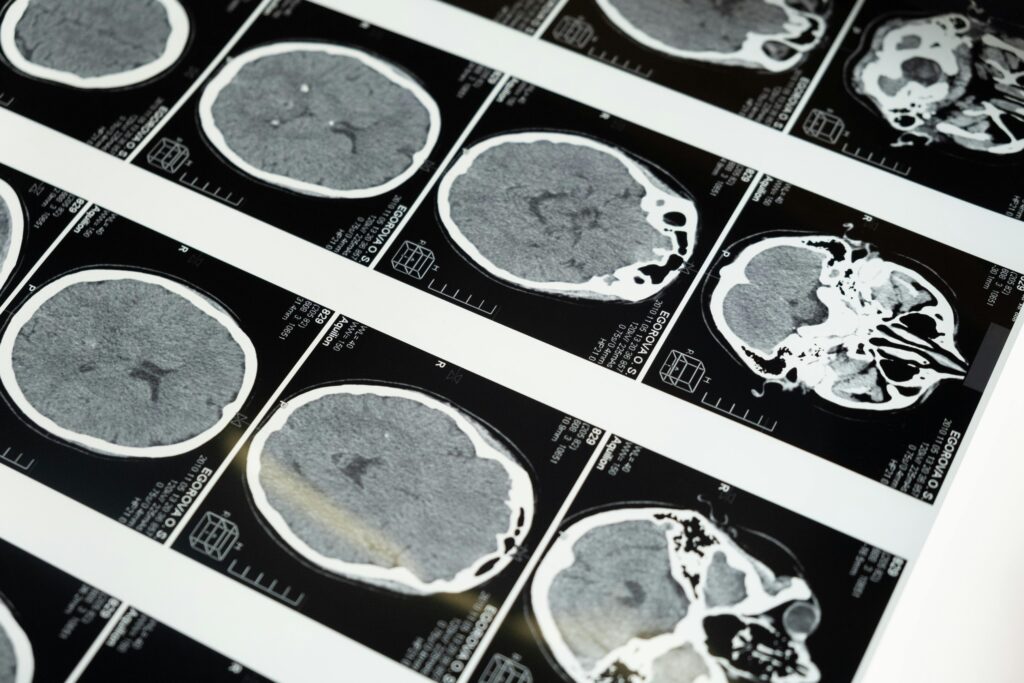

Bases neurobiológicas

La neuropsicología integra los cambios conductuales con los mecanismos cerebrales subyacentes:

• Comienza en el hipocampo y estructuras límbicas relacionadas con la memoria episódica.

• Luego se extiende hacia corteza temporal, parietal y frontal, lo que explica el deterioro progresivo en múltiples dominios cognitivos.